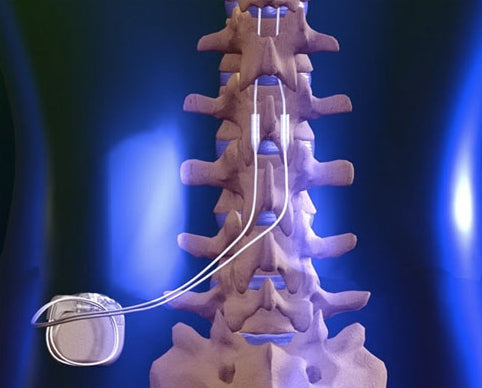

Neuromodulation encompasses peripheral nerve and spinal cord stimulation, and dorsal root ganglion stimulation, treatments that offer hope for individuals struggling with acute and chronic pain who may feel they have no alternatives. By using electrical signals that are uniquely adjusted to the patient’s pain physiology to “modulate” (to change) the patient’s nerve pain, neuromodulation treats the source of the pain directly, enhancing functional mobility while simultaneously decreasing the need for medication.

Neuromodulation is a safe, well-established treatment that has helped patients for over thirty years. Historically, spinal cord stimulation was most commonly prescribed for patients with post-operative pain, now there are many new clinical indications for its use. Please click the links to the right to learn more about the different kind of neuromodulation treatments available.